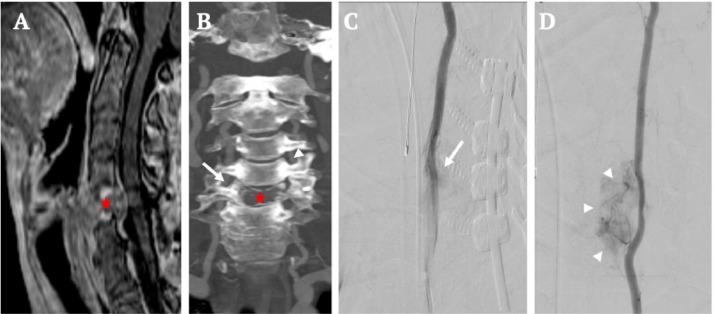

Symptomatic vascular spinal metastases will benefit from pre-operative tumor embolization - percutaneous with or without adjunct endovascular embolization. However, when a transpedicular approach is not feasible, an anterolateral approach may be a viable alternative. The authors report a 57-year-old woman with prior C3-T1 instrumentation who presented with acute cord compression from a pathologic C5 vertebral body fracture related to metastatic renal cell carcinoma. The patient underwent CT-guided direct tumor embolization with 33% n-butyl-2-cyanoacrylate via an anterolateral approach, followed by C5-corpectomy and anterior cervical C4-C6 fusion and plating with minimal blood loss (est. 20 cc) and a stable neurological exam post-operatively. In patients with highly vascular cervical metastatic disease who lack a viable transpedicular approach for preoperative tumor embolization, a CT-guided anterolateral approach is a viable alternative.

有症状的脊柱血管性转移瘤将受益于术前肿瘤栓塞——经皮栓塞,可联合或不联合血管内辅助栓塞。然而,当经椎弓根入路不可行时,前外侧入路可能是一种可行的替代方法。作者报告了一名57岁女性,既往有C3 - T1内固定,因转移性肾细胞癌导致C5椎体病理性骨折,出现急性脊髓压迫。患者通过前外侧入路,在CT引导下用33%的正丁基-2-氰基丙烯酸酯进行直接肿瘤栓塞,随后行C5椎体次全切除、颈前路C4 - C6融合及钢板固定,术中失血极少(估计20毫升),术后神经功能检查稳定。对于高度血管化的颈椎转移性疾病患者,若缺乏可行的经椎弓根术前肿瘤栓塞入路,CT引导下的前外侧入路是一种可行的替代方法。